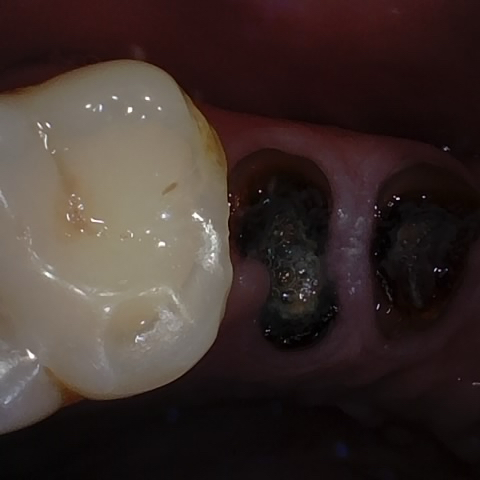

Incorrect Quality Level

The reference annotation for this image is

None

.

Please select the correct quality level.

Annotated as "Good"